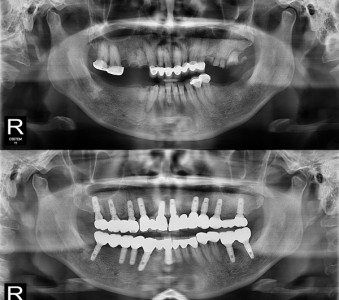

以成果证明实力。

国际摩牙齿科

真实临床案例